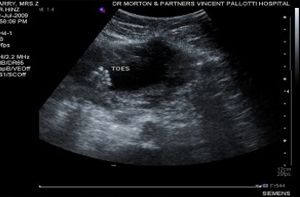

Anyway, we went to the Vincent Palotti hospital for an ultra sound scan and imagine our suprise when we saw a little tiny potato inside her again. These are high resolution scans taken later but as you can see you was expecting a baby that had a little foot (click on the images to enlarge);

The foetal assessment suggested that things were looking promising based on an assessment of baby’s gut, heart, feet and neck width;